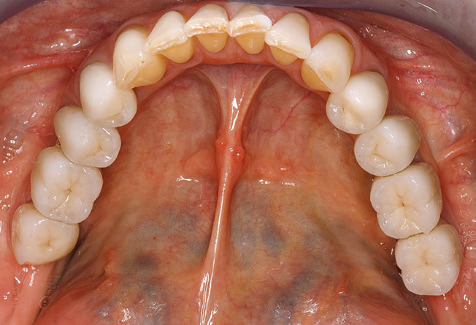

Für den klinischen Langzeiterfolg des parodontal kompromittierten Patienten ist die standardisierte und regelmäßige risikoadaptierte Betreuung im Rahmen der UPT der zentrale Baustein des Behandlungserfolgs. Dies gilt in besonderer Weise für Patienten, die nach erfolgreich abgeschlossener parodontaler Sanierung mit Implantaten versorgt wurden (Abb. 11a und b).

Vor Beginn der prothetischen Versorgung ist es ratsam, den Patienten über die im Rahmen der UPT erforderlichen zeitlichen und finanziellen Aufwendungen (zwei bis viermalige UPT pro Jahr, lebenslang) zu informieren. Dies trägt wesentlich dazu bei, die Compliance des Patienten zu sichern. Darüber hinaus ist die Praxis bei der Bereitstellung der räumlichen und personellen Ressourcen für die Betreuung der parodontal sanierten Patienten gefordert.